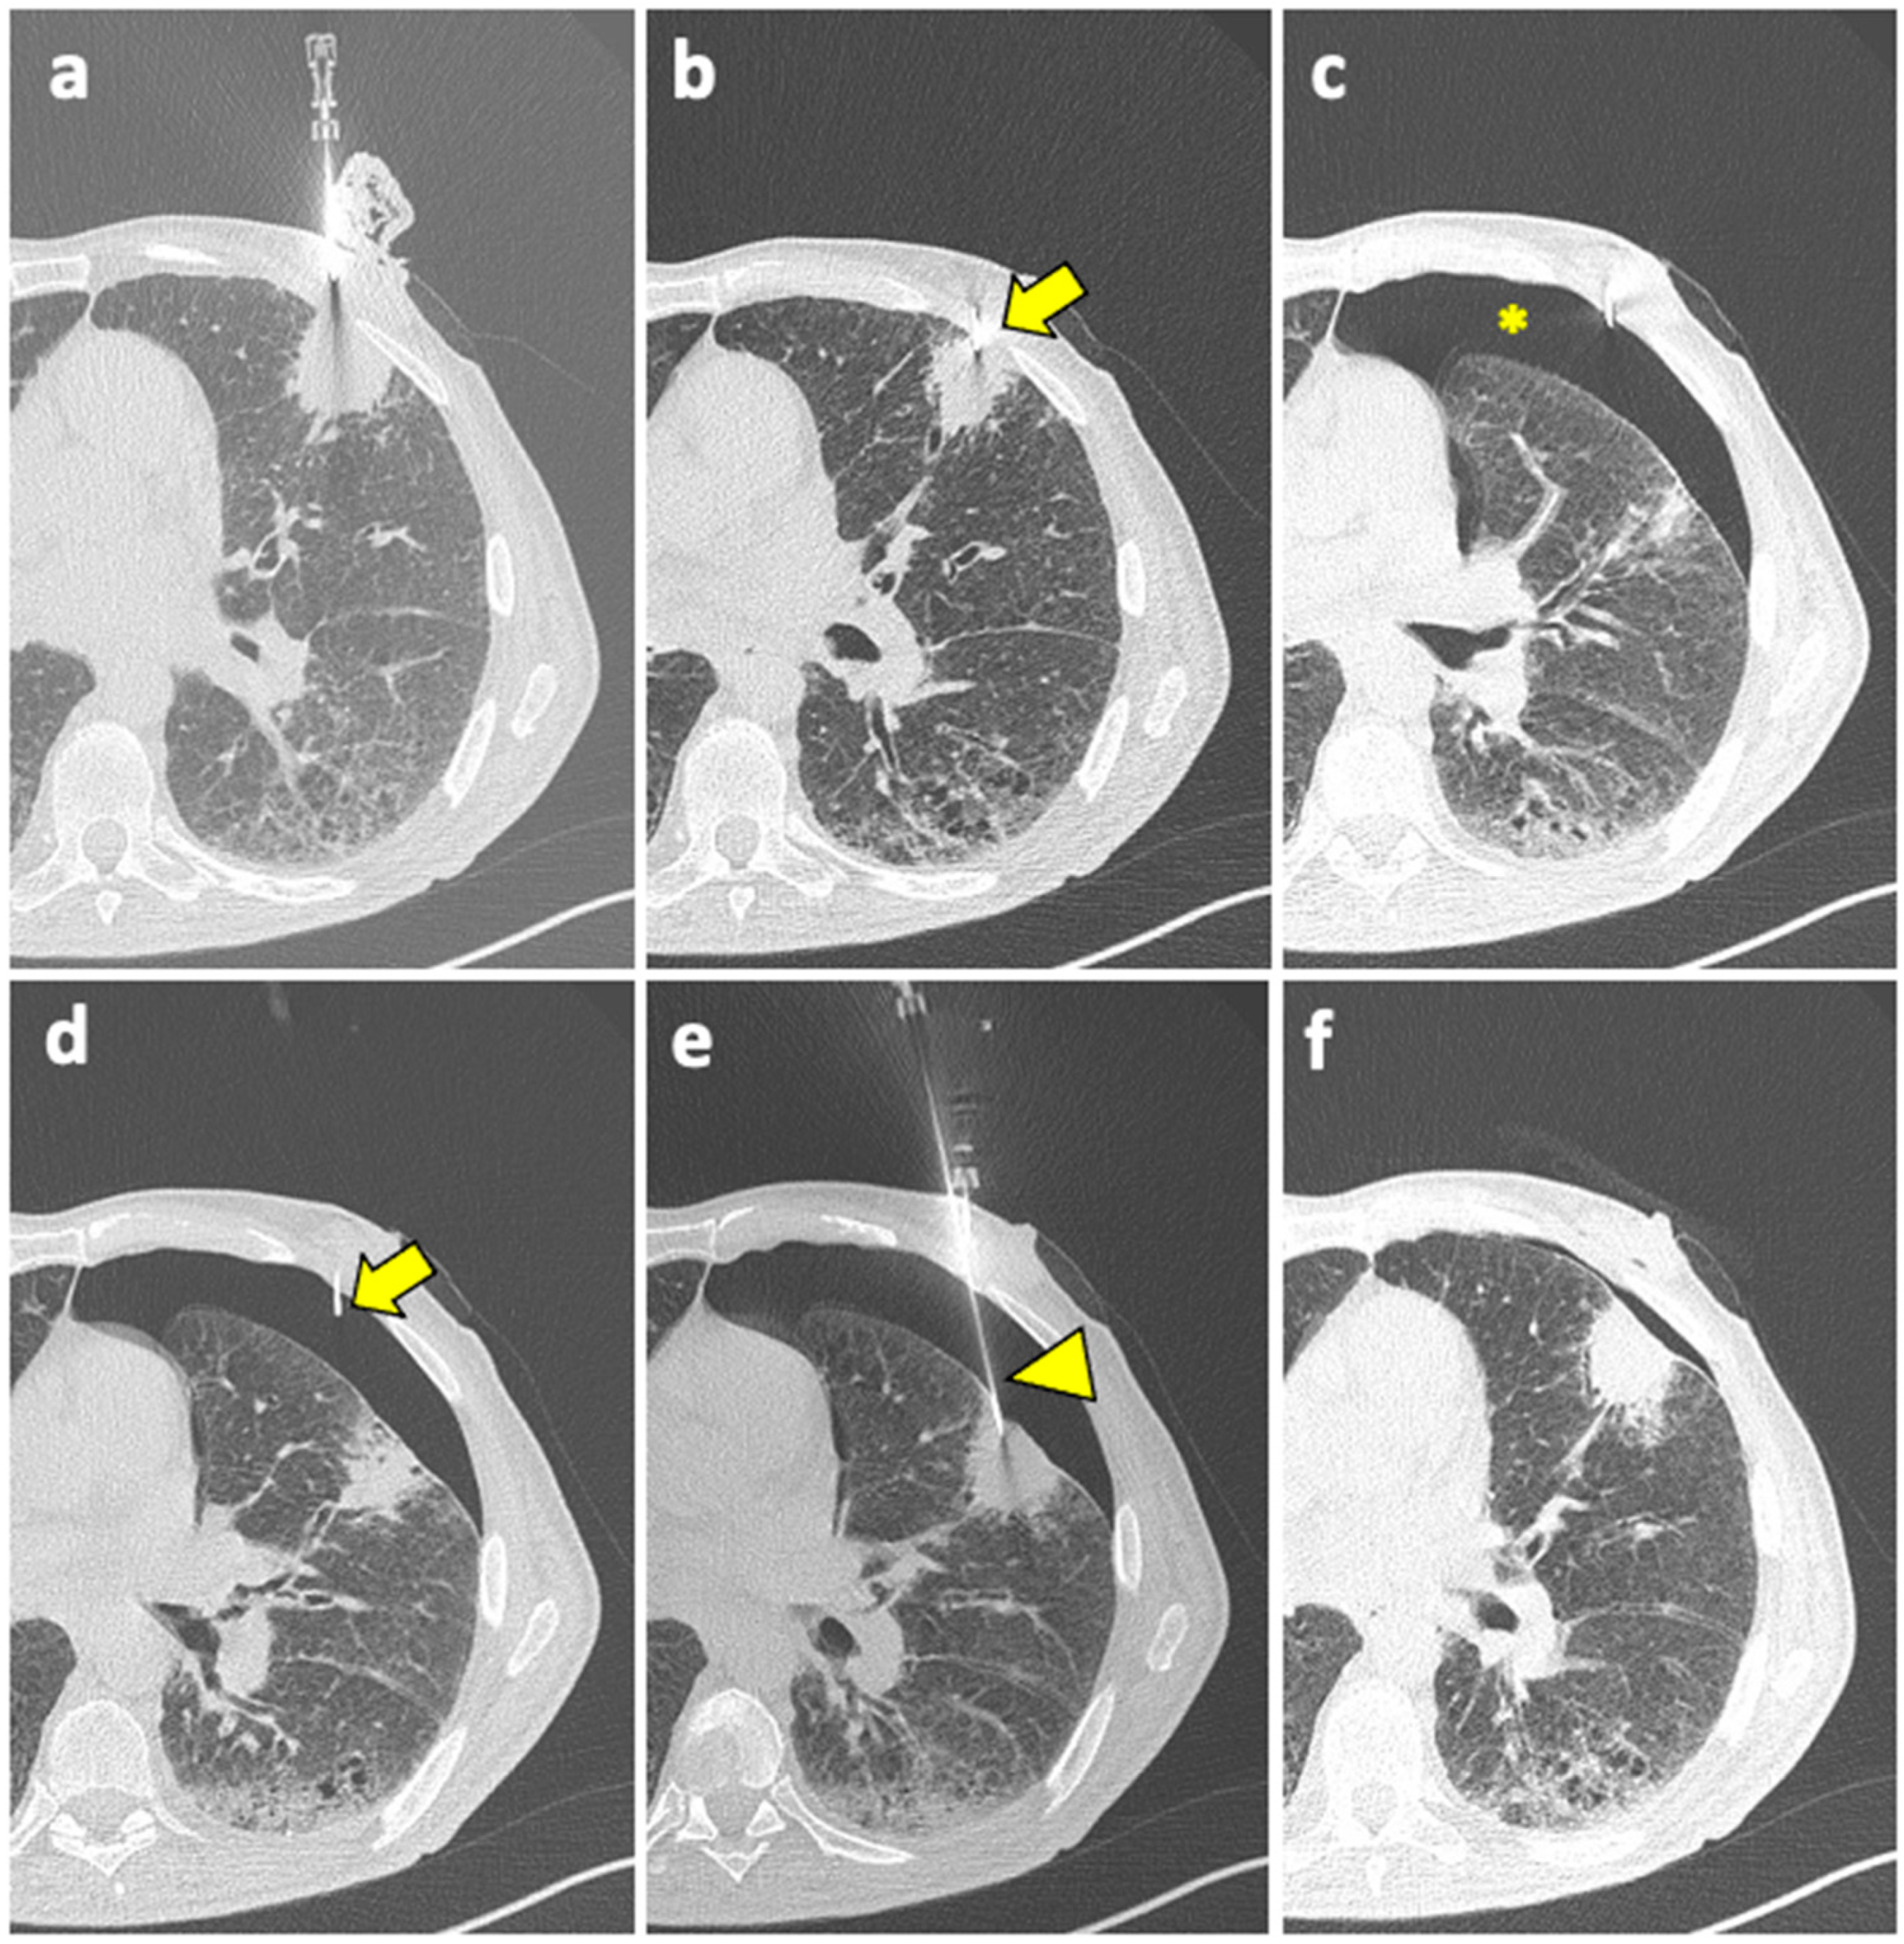

The CBCT system consists of flat-panel fluoroscopy and a CBCT scanner. The execution of CBCT-virtual-navigation-guided lung biopsy is performed in steps. The first step is to acquire a CBCT scan for adequate planning of the biopsy. Briefly, using the software (various software exist, by different vendors), the operator establishes the target lesion and the needle entry point at the skin surface, after which a virtual segment connecting the entry and target points is shown, representing the needle path. On the basis of this planning, the software automatically calculates the correct C-arm position to display the needle entry point on the patient’s skin. This phase of the procedure is called “entry point positioning”. After skin disinfection of the access area, under fluoroscopic guidance, the operator positions the needle tip at the cutaneous entry point, based on the CBCT image appearing on the monitor as a fusion of the 3D volume previously acquired using CBCT and the real-time fluoroscopy bidimensional plane. At this time, the C-arm rotates in the “progression view” position, perpendicular to the previous one. Then, the needle is advanced into the chest to reach the target point, following the virtual path previously determined and displayed on the monitor in real-time fluoroscopy. Then, a second CBCT scan is performed to verify the needle’s correct placement, and the biopsy is taken. A final scan is acquired to assess any complications [124]. An example of CBCT-guided biopsy is illustrated in Figure 4.

This technique overcomes the limits of conventional CT, the lack of real-time monitoring during the puncture, and the lack of flexibility due to the forced choice of the axial plane [65,125,126], allowing for a real-time fluoroscopy visualization of the needle puncture and of the solid lesion movement due to respiration, as well as a free 3D rotation of the C-arm around the patient, leading to the best puncture path [127,128].

CBCT-virtual-navigation-guided lung biopsies are safe and accurate, with a high technical success rate (>99%) and high accuracy (>95%) [127,129]. Moreover, compared to conventional CT guidance, CBCT virtual navigation facilitates needle positioning and reduces the procedural time, the effective X-ray dose [125,129], and the incidence of complications [125]. Moreover, in solid lung lesions smaller than 15–20 mm, its accuracy was higher compared to conventional CT guidance (98.2% vs. 83.7%) [128]. Good results using CBCT guidance in small pulmonary nodules (<1 cm) were also reported by Choo et al., with sensitivity, specificity, and diagnostic accuracy of 96.7%, 100%, and 98%, respectively, with only a 6.5% rate of PNX and 5.6% of hemoptysis [130]. Using CBCT, no significant differences in sensitivity, specificity, and accuracy between the PTLB of nodules <1 cm and larger nodules (from 1 to 2 cm) were found [131].